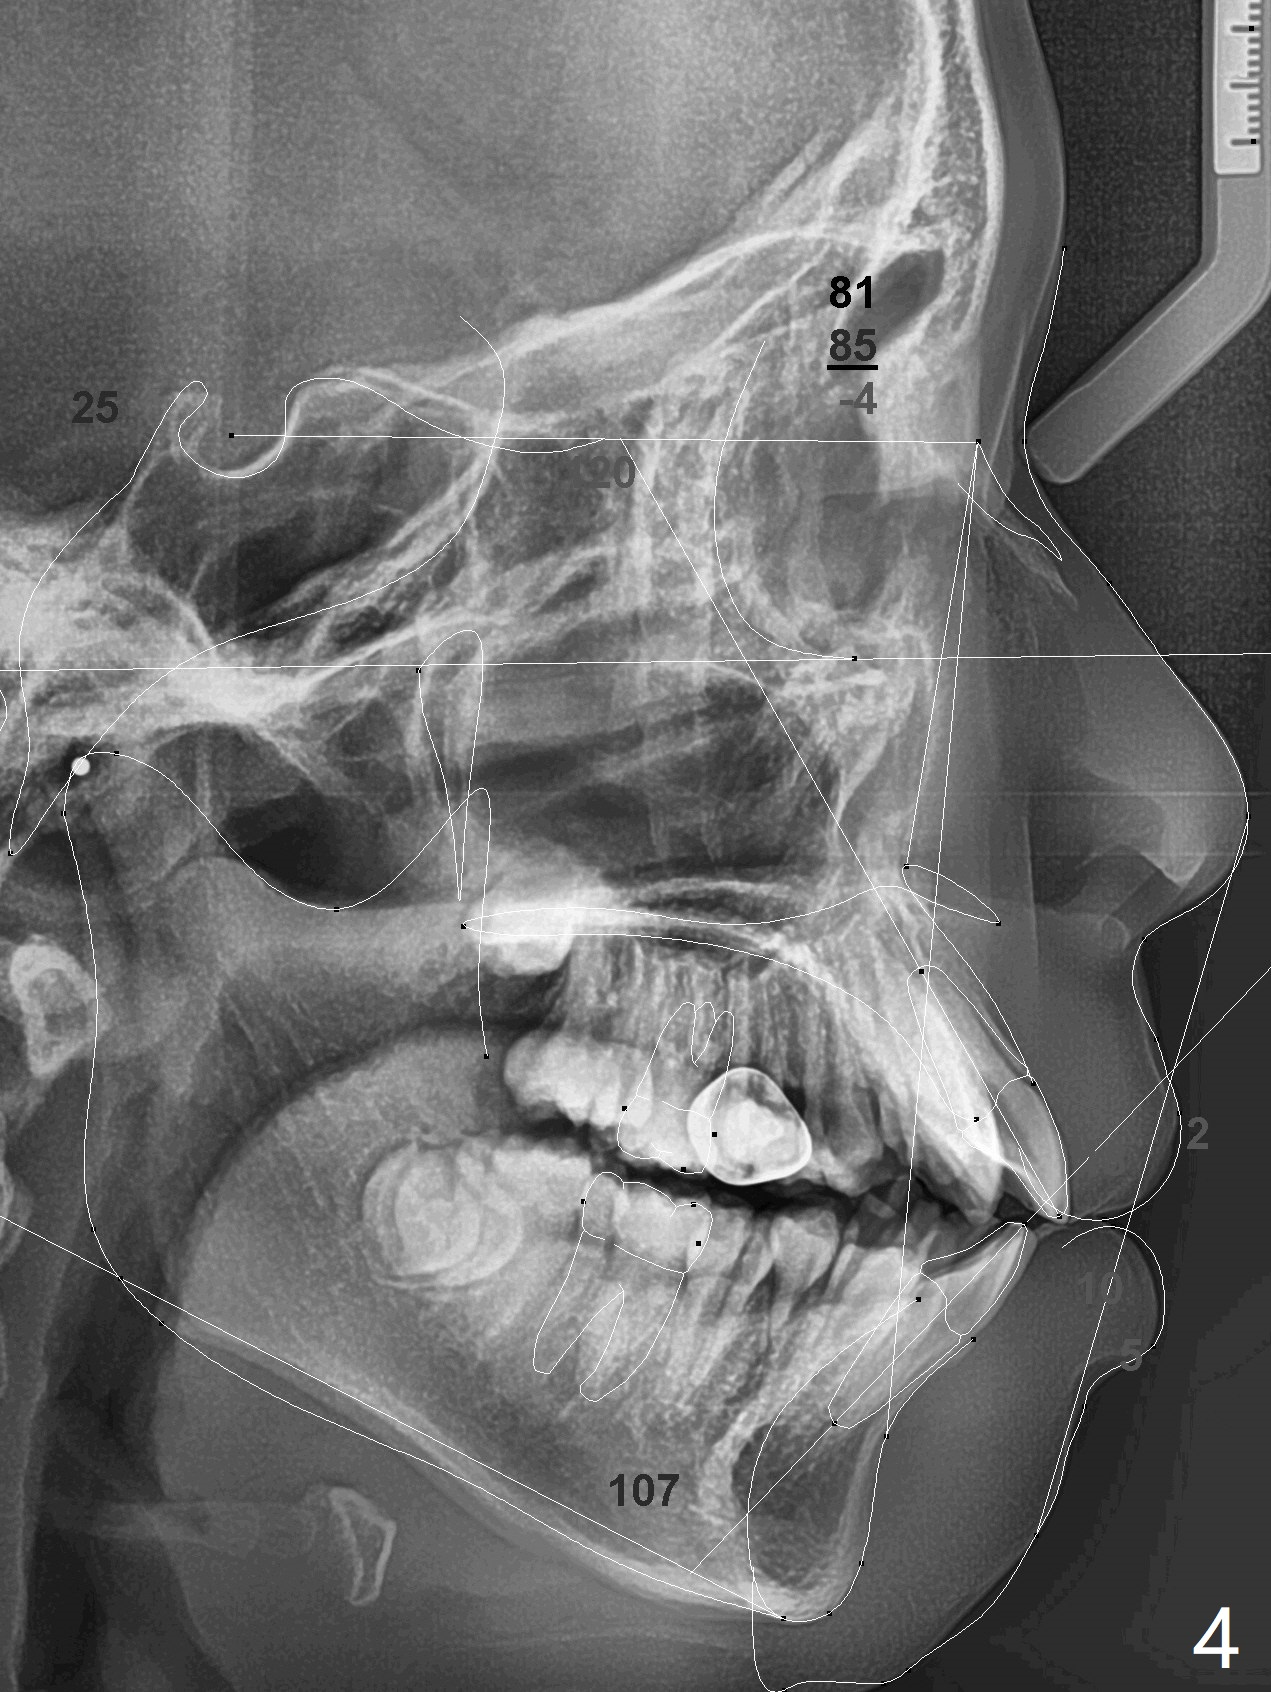

A 13-year-old man has protrusive lips (Fig.1,3,4) with upper midline deviation to the left (Fig.2).  Crowding is severe with LR5 severe lingual inclination (Fig.5,6,10).  To facilitate L6s' uprighting (Fig.10), LR5 and 3 of the 1st bicuspids will be extracted (Fig.6-8 x or *) and molar bands with lingual cleats will be used for the lower.  Cross arch molar retraction will be initiated immediately.  Open coil spring will be placed between UL1 and 3 with the 1st wires to correct the upper midline deviation and to gain the space for UL2.

1) Facial esthetics: looked 'full' and would worsen with non extraction tx/advancement of anterior teeth.

2) Dental open bite

3) U incisor proclination